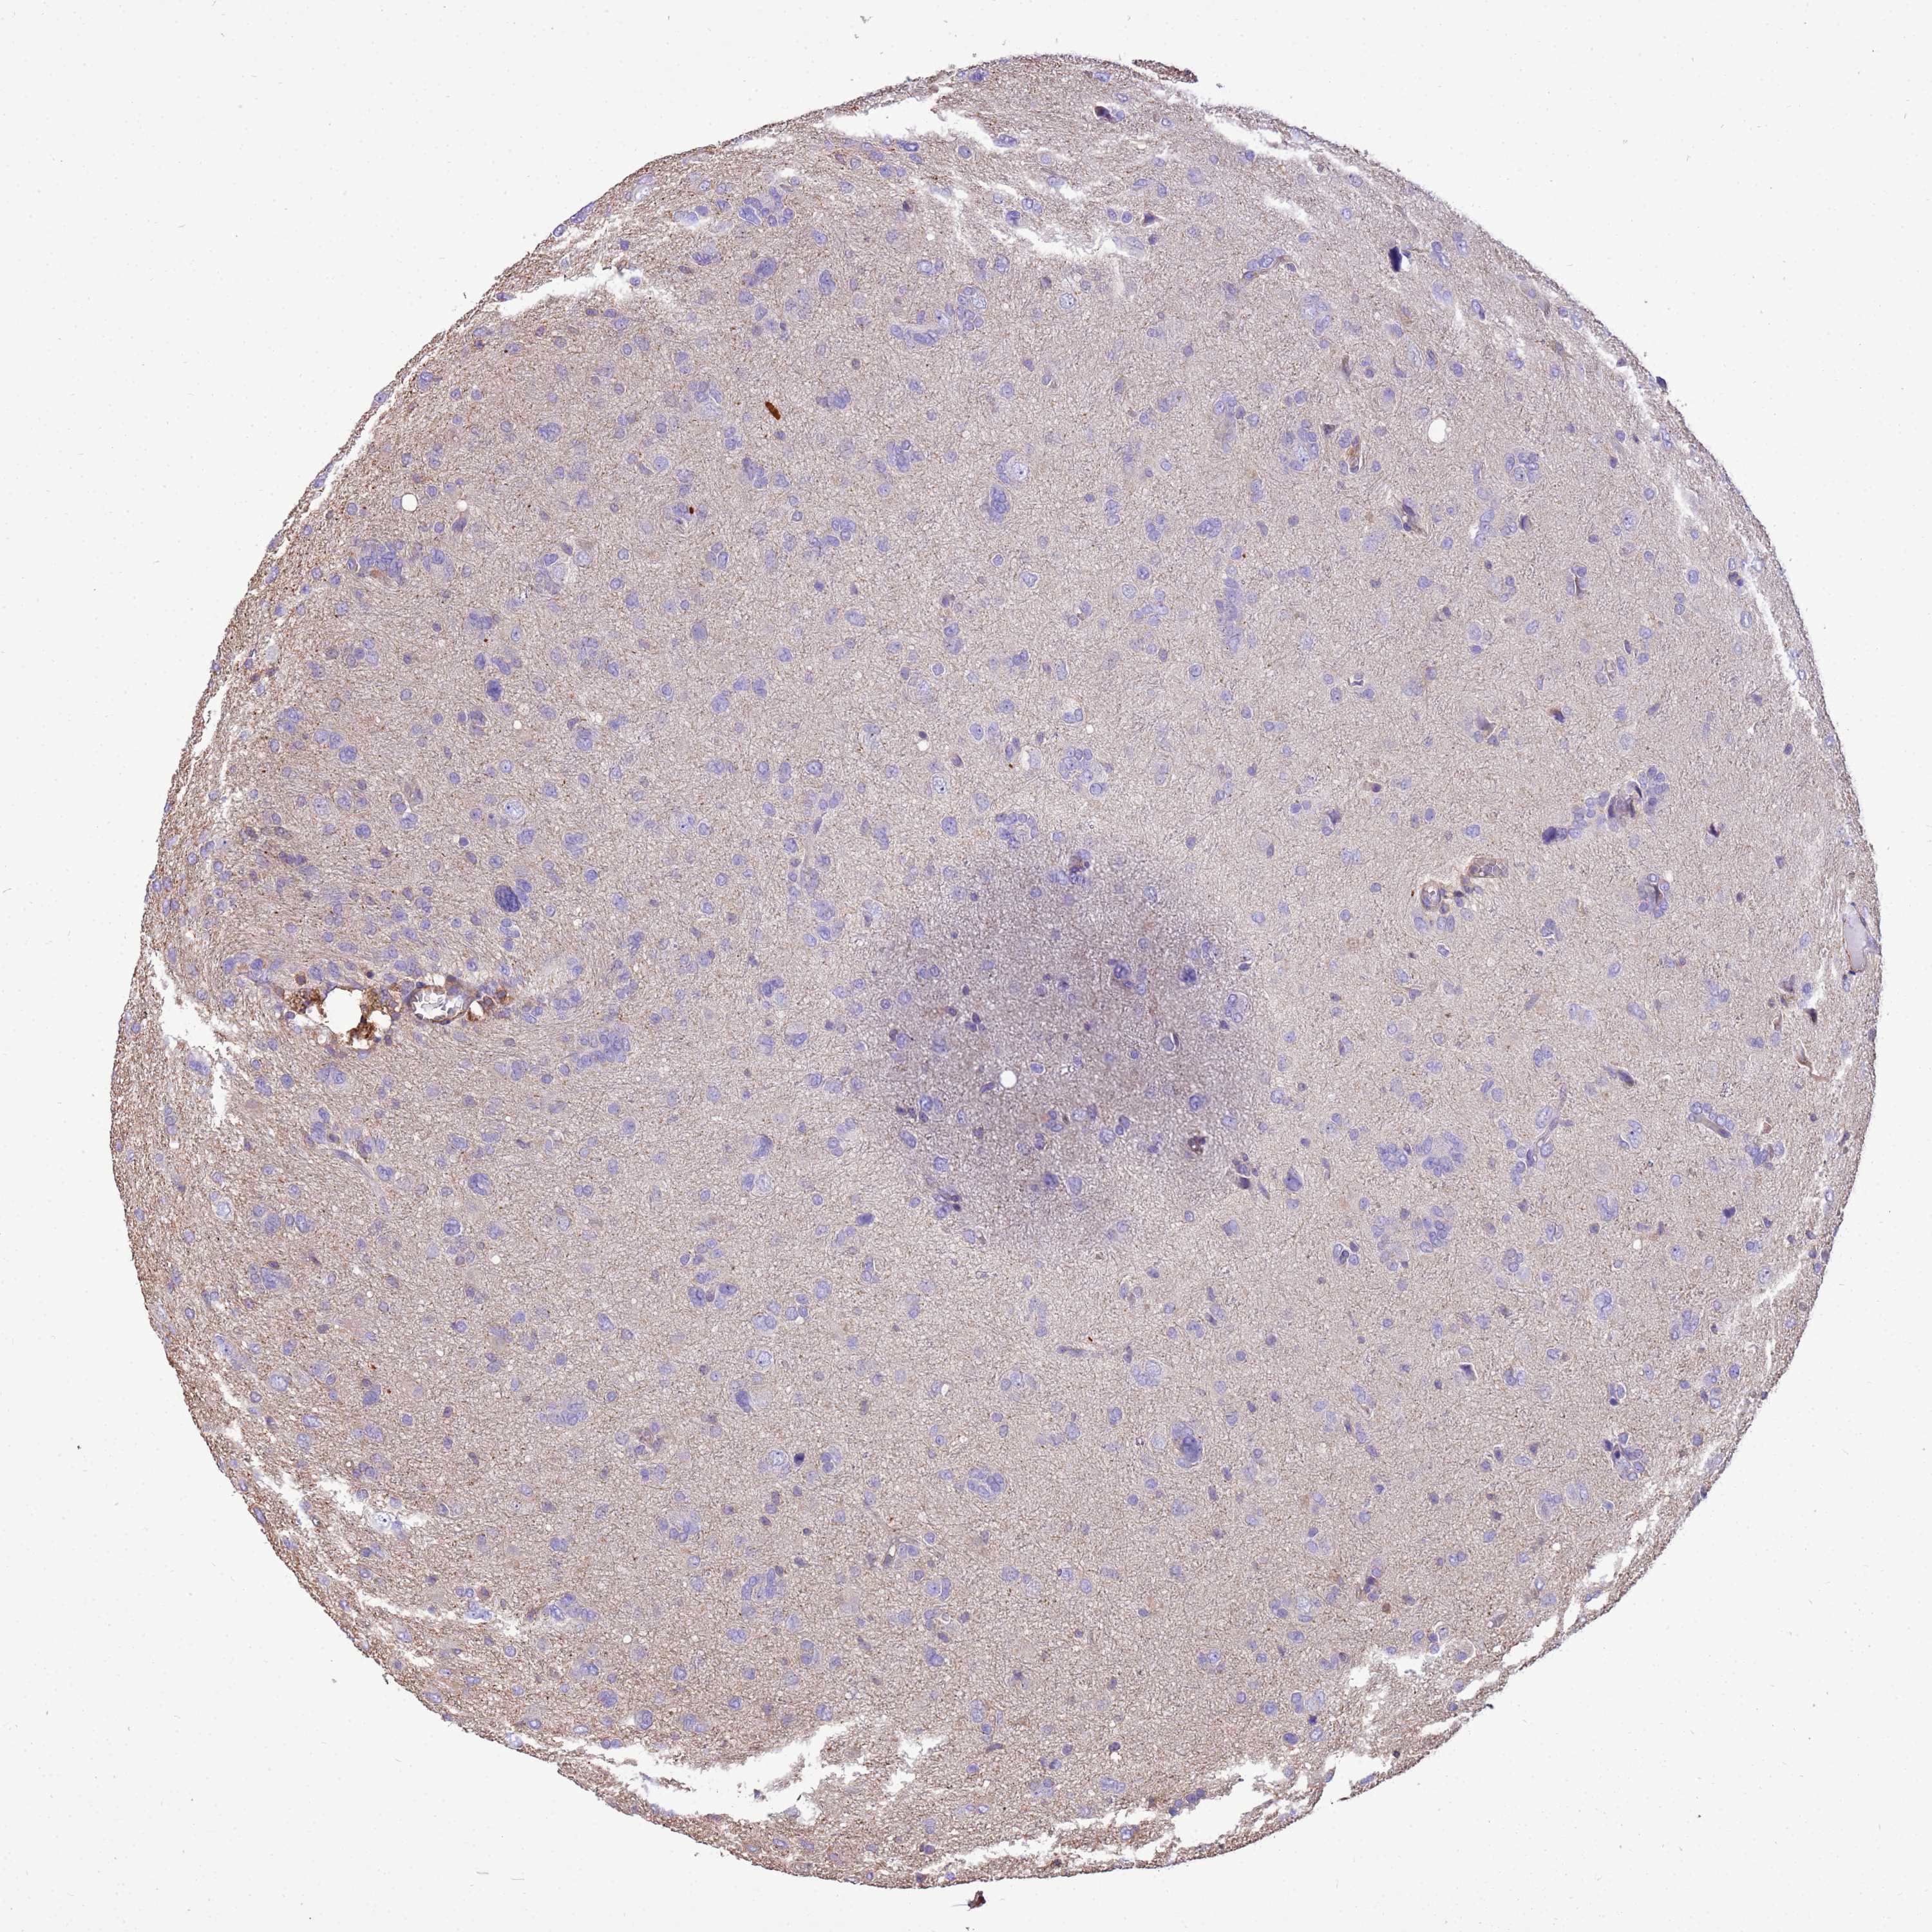

GLIOMA - Protein expressioni

A mouse-over function shows sample information and annotation data. Click on an image to view it in a full screen mode. Samples can be filtered based on level of antibody staining by selecting one or several of the following categories: high, medium, low and not detected. The assay and annotation is described here.

Note that samples used for immunohistochemistry by the Human Protein Atlas do not correspond to samples in the TCGA dataset.

Antibody stainingi

Antibody staining in the annotated cell types in the current human tissue is reported as not detected, low, medium, or high, based on conventional immunohistochemistry profiling in selected tissues. This score is based on the combination of the staining intensity and fraction of stained cells.

Each image is clickable and will lead to virtual microscopy that enables deeper exploration of all samples and also displays staining intensity scores, fraction scores and subcellular localization as well as patient and tissue information for each sample.

Antibody HPA046186

Staining

High

Medium

Low

Not detected

Intensity

Strong

Moderate

Weak

Negative

Quantity

>75%

75%-25%

<25%

None

Location

Nuclear

Cytoplasmic/membranous

Cytoplasmic/membranous,nuclear

Glioma, malignant, Low grade

Glioma, malignant, High grade

Glioblastoma, NOS